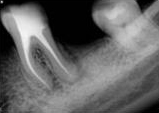

antes depois